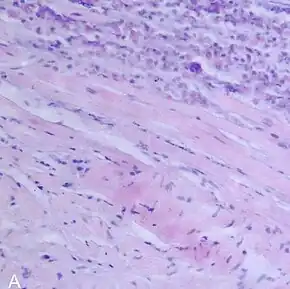

![]() | |

| A microscope image of myocarditis at autopsy in a person with acute onset of heart failure | |